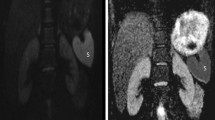

The fiber tracks obtained from the ROIs were qualitatively analyzed for tractography quality, direction of tracks and differences in fractional anisotropy within the renal parenchyma. This assessment was done using two tractography maps: 1) a standard color-coded reconstruction to visualize the orientation of tracks where blue tracks represented diffusion in the craniocaudal direction, green tracks characterized diffusion in the anteroposterior direction and red tracks showed diffusion in the transverse direction, and 2) a scalar fractional anisotropy map with minimum and maximum fractional anisotropy thresholds of 0.1 and 0.6, respectively.

The extension of tracks following the psoas muscle or into adjacent organs (liver for the right kidney or spleen for left kidney) was recorded. The radial distribution of tracks was evaluated with a 3-point scale: 1) clear radial organization of fibers, 2) partial radial organization of fibers with random non-organized fibers and 3) non-radial organization pattern (Fig. 3). The corticomedullary differentiation on the scalar tractography fractional anisotropy maps was also assessed (Fig. 4).

The grading of degree or track organization is illustrated on diffusion tensor imaging in three subjects. a Normal right kidney in a 5.5-year-old boy with clear radial distribution of tracks. b Left kidney with ureteropelvic junction (UPJ) obstruction and grade 4 pelvicalyceal dilatation in a 6.6-year-old boy with partial radial organization of fibers. c Left kidney with UPJ obstruction and grade 5 pelvicalyceal dilatation in a 12.4-year-old boy with non-radial organization of fiber tracks

Tractography artifacts

Tractography artifacts. a Color-coded fiber tractography map overlaid on sagittal diffusion-weighted image (DWI) shows a normal kidney in a 1-year-old boy. Note the blue tracks following the normal anatomy of the psoas muscle (arrow). Fibers within the kidney depict a clear radial organization pattern. b Color-coded fiber tractography map overlaid on coronal DWI shows a kidney with ureteropelvic junction obstruction and grade III pelvicalyceal dilatation in a 6.2-year-old girl. Red tracks extend from the renal parenchyma into the spleen. Fibers within the kidney depict partial radial organization with some random non-organized fibers